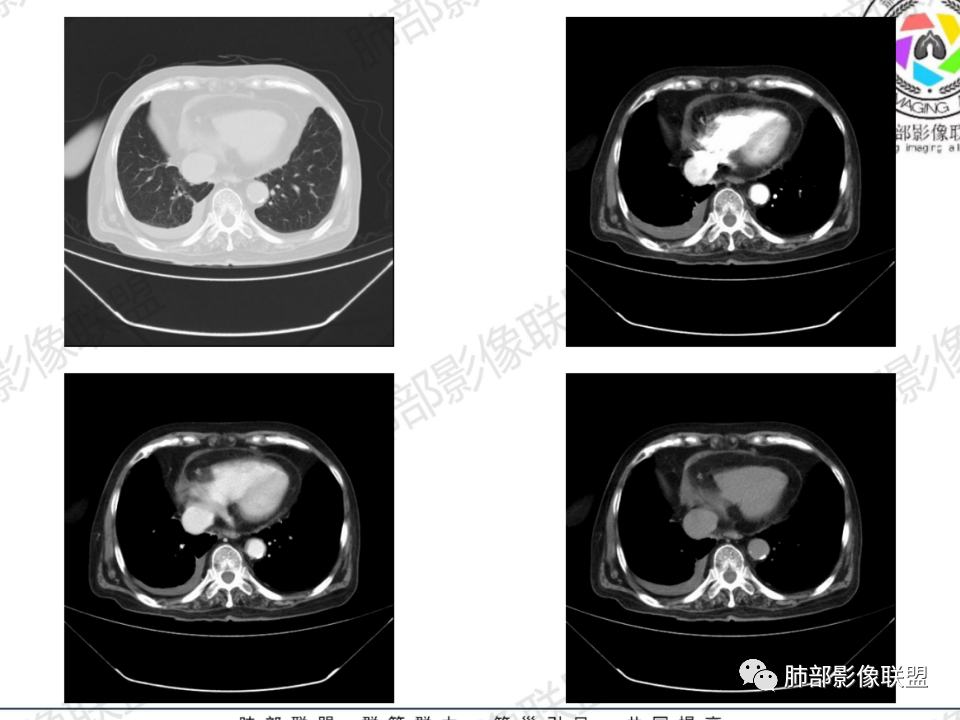

那个人:老年女性,亚急性病程,咳嗽发热。有垂体前叶功能减退,目前激素替代治疗,长期激素,量小,不知道累积量,没有目前激素水平指标。既往有淋巴结结核病史。肿瘤标记物Ca125升高。血沉升高,C反应蛋白轻度异常。影像,右肺上叶靠近肺门团块影,右肺门淋巴结钙化肿大,支气管狭窄,局部增厚,团块影外朝内改变,强化明显,血管破坏不明显,有粘液。和纵隔胸膜分界清楚,周围肺组织有斑片渗出影,右侧胸腔积液,考虑炎性?结核?支气管镜检查除外恶性飞鹰行动:老年患者,影像表现 右肺上叶占位性病变,边界清楚,有分叶征,内见细小钙化,右肺上叶支气管截断,增强病灶不均匀强化,病灶内有条状坏死区(扩张的支气管?),纵膈内未见增大淋巴结,考虑炎性病变,结核可能。一切∮随缘:右肺上叶实性肿块形态不规则,呈三角形,边缘分叶,边界伴有磨玻璃影,近段支气管未见明显显示,可能堵塞,病变平扫密度均匀,增强后可见低密度坏死无强化,周围略强化,右肺下叶散在结节。心包积液,及右侧胸腔积液,临床:有低热,低蛋白血症,肿瘤标记物高,考虑恶性:腺癌,神经内分泌癌(强化偏弱了),淋巴瘤,鉴别:结核红星:老年女性患者右肺上叶,肺门上区 分叶状肿块 ,右肺上叶支气管显示不清,增强扫描肿块,中等程度强化可见小斑片状坏死区,病灶内部可见斑点状钙化灶,病灶周围可见斑片状及小斑点状影,纵膈淋巴结增大,其他区域,胸膜下可见斑点状钙化。考虑肉芽肿性病变,结核的可能性大。老年患者最排除肿瘤性病变腺癌。土娃:右上肺不规则肿块影,边缘分叶,边界磨玻璃影欠清,病灶分叉状,内见点状钙化影及坏死灶,支气管堵塞,病灶增强强化不明显。考虑瘤样结核,鉴别淋巴瘤。张小兵:老年女性,亚急性病程,右肺上叶见不规则肿块,边缘平直凹陷为主,周围GGO边界不清,内见点状钙化及坏死灶,增强持续性渐进强化,右侧少量胸腔积液,双肺门及纵隔肿大淋巴结伴钙化,综合考虑慢性炎症。saf:老年患者,影像表现 右肺上叶占位性病变,边界清楚,有分叶征,增强病灶明显不均匀强化,纵膈内未见增大淋巴结,考虑炎性病变,结核可能。小兜:老年女性,咳嗽喘息一月,发热三天,肿瘤标志物升高,长期激素替代治疗。CT示右肺上叶近肺门不规则实变影,周围伴磨玻璃影,增强持续性渐进强化,内部血管破坏不厉害,内部可见多发条形低密度灶,右侧胸腔可见少量积液,双肺门及纵隔可见钙化淋巴结,考虑为炎性病变,结核可能玫:女,79咳嗽,喘息一月,发热三天入院,右肺上叶不规则形软组织密度肿块影,边界清晰,边缘见分叶及细短毛刺,病灶内见点状钙化影及稍低密度区,病灶边缘呈磨玻璃样改变,增强扫描,病灶呈不均匀性强化,考虑炎性病变,鉴别鳞癌。大雄:老年女性,既往诊断淋巴结结核,提示已治愈,近2年服用激素,诱导结核复燃→发热;纵隔肺门淋巴结肿大钙化,压迫支气管,右肺上中下叶支气管均狭窄→喘息咳嗽;尖段支气管受累闭塞→肺不张、支气管粘液栓;累及胸膜,结核性胸膜炎并胸水→右侧胸痛;实验室,血沉快,CA125高,低蛋白,符合;下一步,支气管镜尖段支气管刷检抗酸染色周太狼:老年女性,亚急性病程,肿瘤标志物升高。CT示右肺上叶尖段不规则肿块影,有分叶、收缩,周围伴磨玻璃影,增强渐进强化,内部可见多发条形低密度灶,右侧胸腔及心包少量积液,纵隔内淋巴结稍增大。倾向于恶性病变,肺癌伴阻塞性炎变可能。丽:老年女性,右肺上叶不规则软组织肿块,边缘清晰,内密度不均,可见点状钙化及粘液栓,周围可见片状高密度影,增强后均匀强化,内多发低密度,纵膈多发钙化淋巴结,考虑结核可能大,建议结合支气管镜检查除外肿瘤宇宙:右胸廓缩小,右肺上叶团块影及不张,平直边,周围磨玻璃影,纤细胸膜牵拉,上叶尖段支气管堵塞,明显延迟强化,可见支气管粘液栓,两肺门钙化淋巴结,右侧胸水,考性炎性肉芽肿,鉴别腺癌王秀仙:右肺上叶肺门区肿块,上叶支气管开口阻塞,形态不规则,密度不均,内可见支气管粘液栓及多发小灶性坏死,周围磨玻璃影边缘模糊,渐进强化,右侧胸腔积液、胸膜钙化,考虑炎性肉芽肿性病变,慢性炎症。鉴别鳞癌,结核。刘丹:老年女性,右肺上叶肿块伴钙化,右肺上叶支气管截断,增强后均匀强化,周边可见点片状模糊影,右侧胸腔积液,右肺门淋巴结增大,考虑占位并阻塞性炎症,肿瘤?结核?建议纤支镜检查。小飞:右肺上叶纵隔旁软组织肿块,边缘深分叶、长毛刺及毛刷样短毛刺,边缘磨玻璃影,磨玻璃边界模糊,支气管截断,平扫密度不均,可见点状钙化,增强不均匀明显强化,心影增大,心包积液,右侧胸腔积液,考虑恶性肿瘤,腺癌?秦化君:右肺上叶不规则分叶软组织密度肿块,边缘清晰,胸膜牵拉,周围花花草草,上叶尖段支气管阻塞,内可见点状钙化,增强后密度不均可见支气管粘液栓及坏死区,内见血管分枝。中间段及中叶,下叶支气管狭窄,壁见钙化。右肺门淋巴结肿大,右侧胸腔积液,心包粘连肥厚。考虑1右上肺恶性病变,鳞癌?2右肺多叶段支气管狭窄,考虑支气管内膜结核?3胸腔积液及肺门淋巴结肿大,转移?风儿:老年女性,右肺上叶肿块,形态不规则,外围大内带小,边缘分叶膨隆平直及毛糙,密度不均,内见支气管粘液栓及多发小灶性坏死,坏死边缘清晰 ,渐进强化,上叶尖段支气管阻塞,叶支气管壁有局限性增厚,邻近胸膜腔微积液;纵隔及双肺门淋巴结肿大,部分钙化,右侧胸腔积液、心包积液、胸膜钙化,考虑炎性,肉芽肿性结核可能性大。鉴别鳞癌,女性及血供均不支持;腺癌,坏死边界太清晰。流心明智:老年女性,79岁,咳嗽、气短1月,发热3天。胸CT:右肺上叶见不规则肿块,边缘有膨隆、有平直凹陷,周围GGO边界不清,病灶内见点状钙化、粘液栓,尖段支气管未见,增强持续性渐进强化,右侧少量胸腔积液,双肺门及纵隔肿大淋巴结伴钙化,肺动脉增粗。考虑:右上叶尖段堵塞并慢性炎症,支气管TB并结石?鉴别Ca

支气管壁增厚,周围磨玻璃边界不清,提示炎症。胸膜下钙化符合结核

背段支气管周围增厚伴钙化,符合结核改变

胸腔积液并胸膜钙化,符合结核;

结核是肯定有。现在最大问题是尖段

近端显示不清,但是远端是粘液栓,可以认为是还行的

如果是近端鳞癌,远端应该会堵塞,不会整个肿块里面还有较为通畅的支气管

这个区域我们看到密度与周围一致,并不是肺癌伴周围不张的感觉,所以鳞癌暂时是不支持的

临床信息:老年女性,亚急性病程,咳嗽发热。有激素使用史。既往有淋巴结结核病史。肿瘤标记物Ca125升高。血沉升高,C反应蛋白轻度异常。 影像所见:右侧胸廓相对狭小,右肺上叶不规则团块影贴附纵隔旁,轻度分叶,整体密度较均匀,偶见钙点。

相应上叶尖端及前段支气管开口未能追踪(阻塞),开口处见钙化。病灶渐进性强化,并衬托出较完整尖段及前段含液支气管影。支气管开口区域未见异常高密度强化(如类癌等)及相对乏血供区(如鳞癌)。病灶区未见液化坏死。右上纵隔及胸廓入口区未见病灶胸膜外突破(栽赃)。

右肺上叶后段等区域散在片状影,边界不清(提示渗出性病灶)。

纵隔及双肺门见钙化淋巴结。心包积液,右侧胸腔积液(提示存在活动新病灶)。双侧胸膜下见多发斑点状钙化,胸廓变形(提示存在结核基础病变可能)。 诊断意见:综上,右肺上叶块状影更符合继发性肺结核。 最后小结:既往诊断淋巴结结核,提示已治愈。近2年服用激素,可疑诱导结核复燃,也可引起发热。纵隔肺门淋巴结肿大钙化,压迫支气管,右肺上中下叶支气管均狭窄,所以引起喘息咳嗽。尖段支气管受累闭塞,导致肺不张、支气管粘液栓,出现条状无强化区。病变累及胸膜,导致结核性胸膜炎并胸水,引起右侧胸痛。实验室检查血沉快,CA125高,低蛋白,均符合结核。下一步,建议支气管镜尖段支气管刷检并抗酸染色。(本段摘自於雄老师精彩发言)